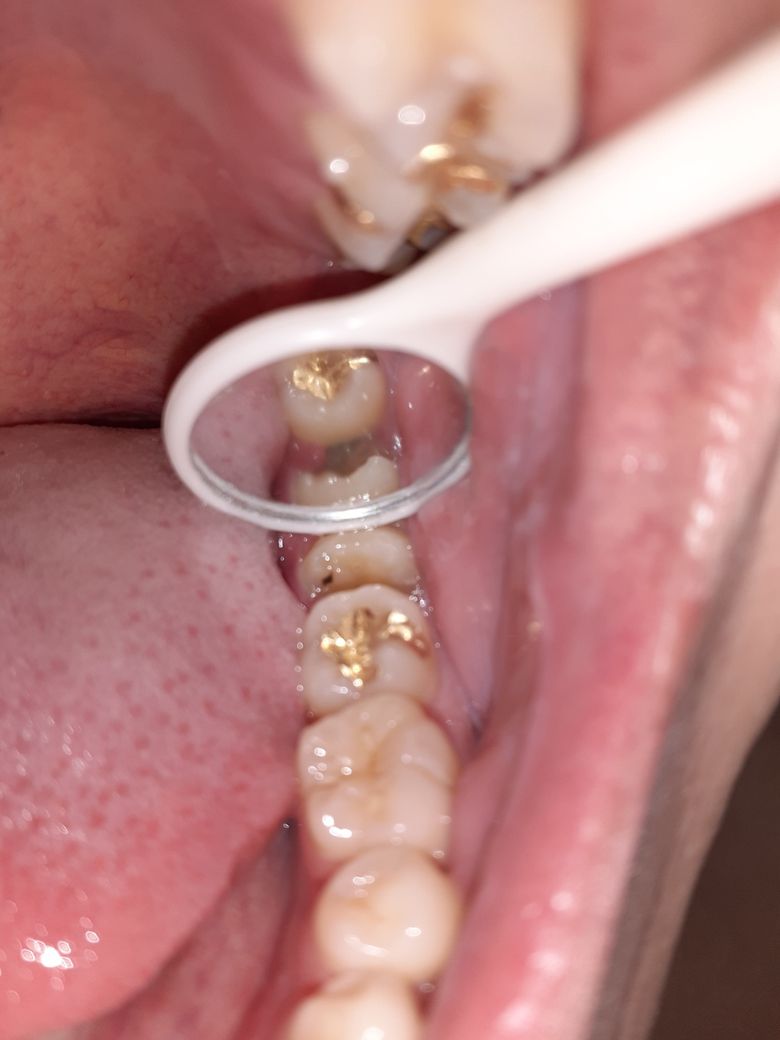

사랑니 부근 잇몸 색깔 검게 변함

사랑니 부근 잇몸이 이렇게 검게 변하였습니다. 지금도 그렇고 이전에도 그렇고 통증이나 그런거는 없었는데 원인이 무엇인가요?.

• 1번 째 사진